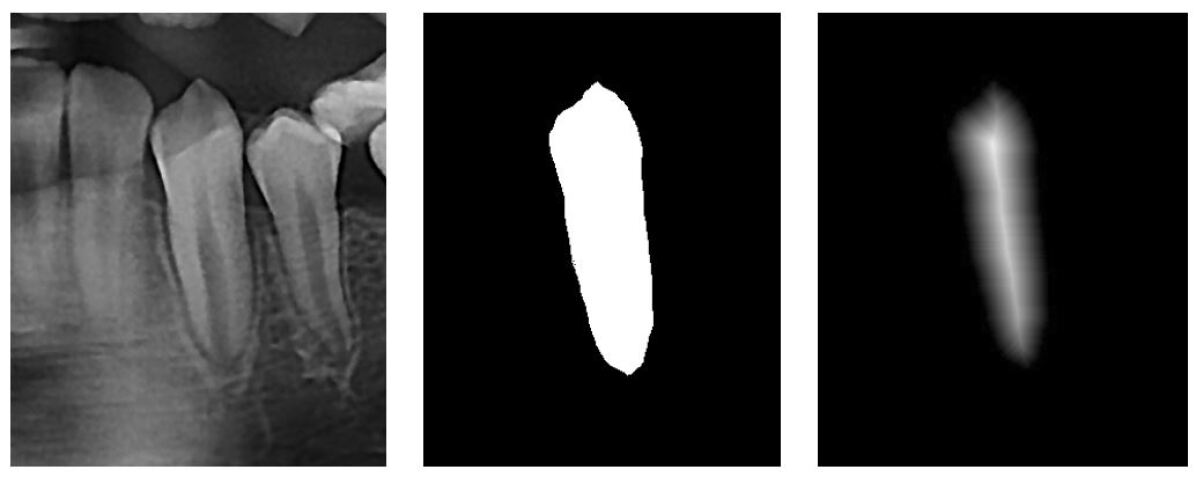

Refer to caption

Figure 4: Two-dimensional visualization of distance map: (left) tooth image patch; (middle) ground truth mask; (right) distance map.

For individual tooth segmentation, we initially cropped the CBCT image into image patches using the detected bounding boxes, and subsequently fed the patches to the segmentation network. However, a simple pixel-wise classification method for tooth segmentation can yield several false positives because every image patch includes partial overlaps between the adjacent teeth. In this study, similar to [2], a distance-based segmentation method was employed for accurate tooth segmentation. The pixel-wise classification task is converted to a pixel-wise distance regression task, where the distance is defined by the shortest 3D Euclidean distance from the surface of the tooth. Accordingly, for training the distance map regression, we used MSE loss instead of BCE loss, which is defined as